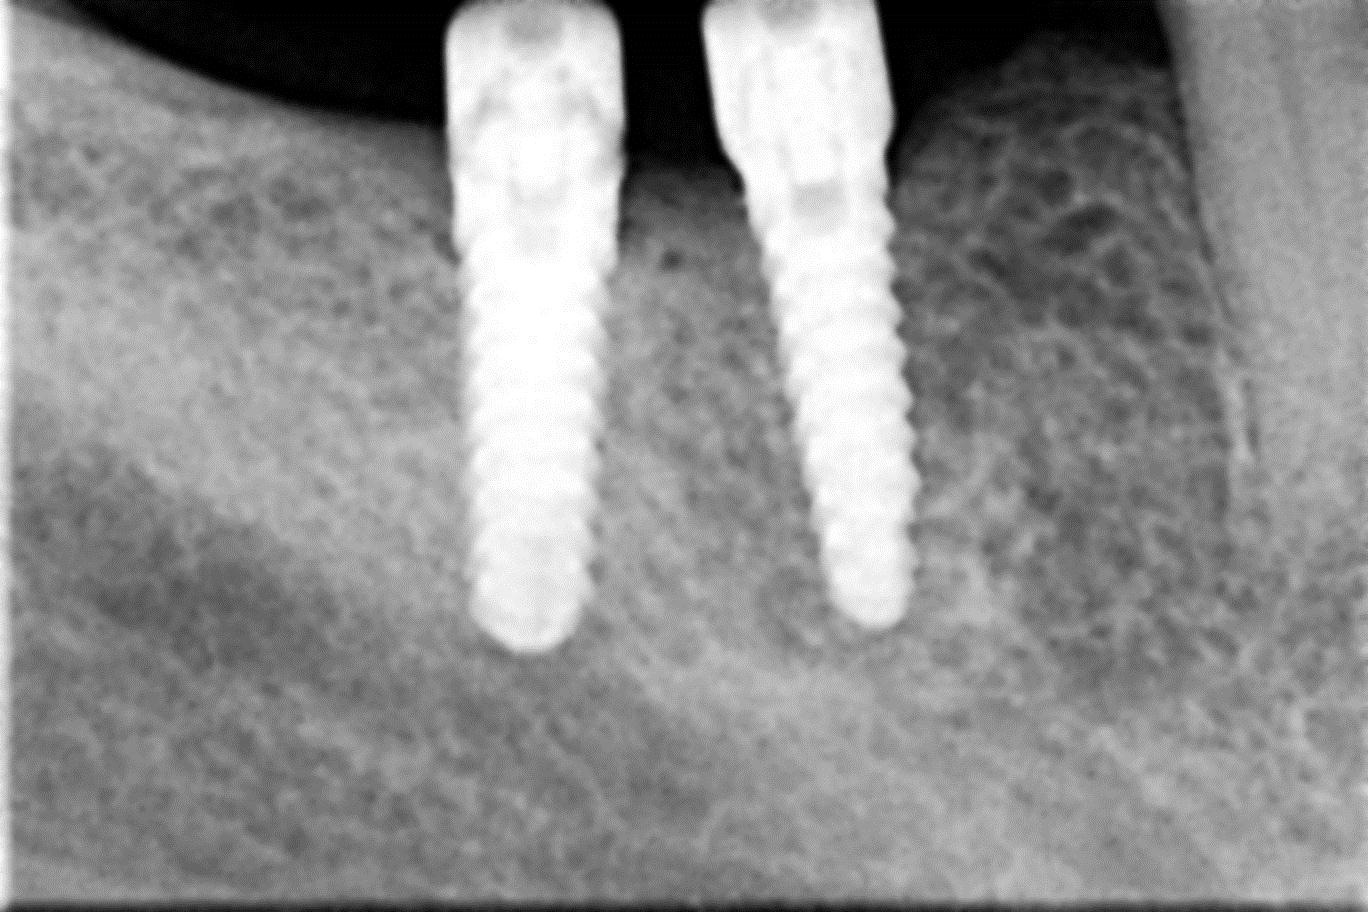

• Zavedení implantátu do kosti čelisti

• Zahojení do kosti – 3-4měsíce(v některých případech i déle – doplňování kosti)

Základní podmínkou pro ošetření pomocí implantátů je dostatečné množství zdravé, kvalitní kosti v čelistech. Dalším důležitým předpokladem je dokonalá ústní hygiena. Také celkový zdravotní stav pacienta hraje významnou roli. Některá systémová onemocnění, jako je diabetes, hypertenze, onemocnění žláz s vnitřní sekrecí, užívání některých skupin léků apod. mohou v některých případech ovlivnit úspěšnost implantace. Také nadměrné kouření či užívání alkoholu nebo jiných návykových látek mohou způsobit komplikace při ošetření pomocí implantátů. Vždy je nutné o těchto záležitostech informovat svého zubního lékaře!

Zavedení implantátů do kosti je většinou ambulantní chirurgický výkon, srovnatelný s vytržením zubu a většinou se provádí v lokální anestézii. Ve výjimečných případech je možné použít i analgosedaci či celkovou narkózu. Operaci provádí zubní lékař-implantolog při dodržení všech podmínek sterility pro operaci. Nástroje pro tuto operaci jsou konstruovány tak, aby výkon byl šetrný vůči kosti a zavedení implantátu bylo provedeno ve velmi krátké době. Díky kvalitní anestézii je výkon nebolestivý. Aby byl pooperační otok co nejmenší, je potřeba operovanou oblast chladit, dle poučení ošetřujícího lékaře. Lékař také ordinuje podle potřeby léky na bolest, případně antibiotika.

Průměrná doba hojení implantátů před provedením definitivního protetického ošetření je 3-4 měsíce, v případech, kde je nutné doplnit chybějící kost (různé metody, postupy a materiály) – tzv. augmentace) se může doba hojení prodloužit na 8-12 měsíců. S tím je pacient vždy předem seznámen svým lékařem.